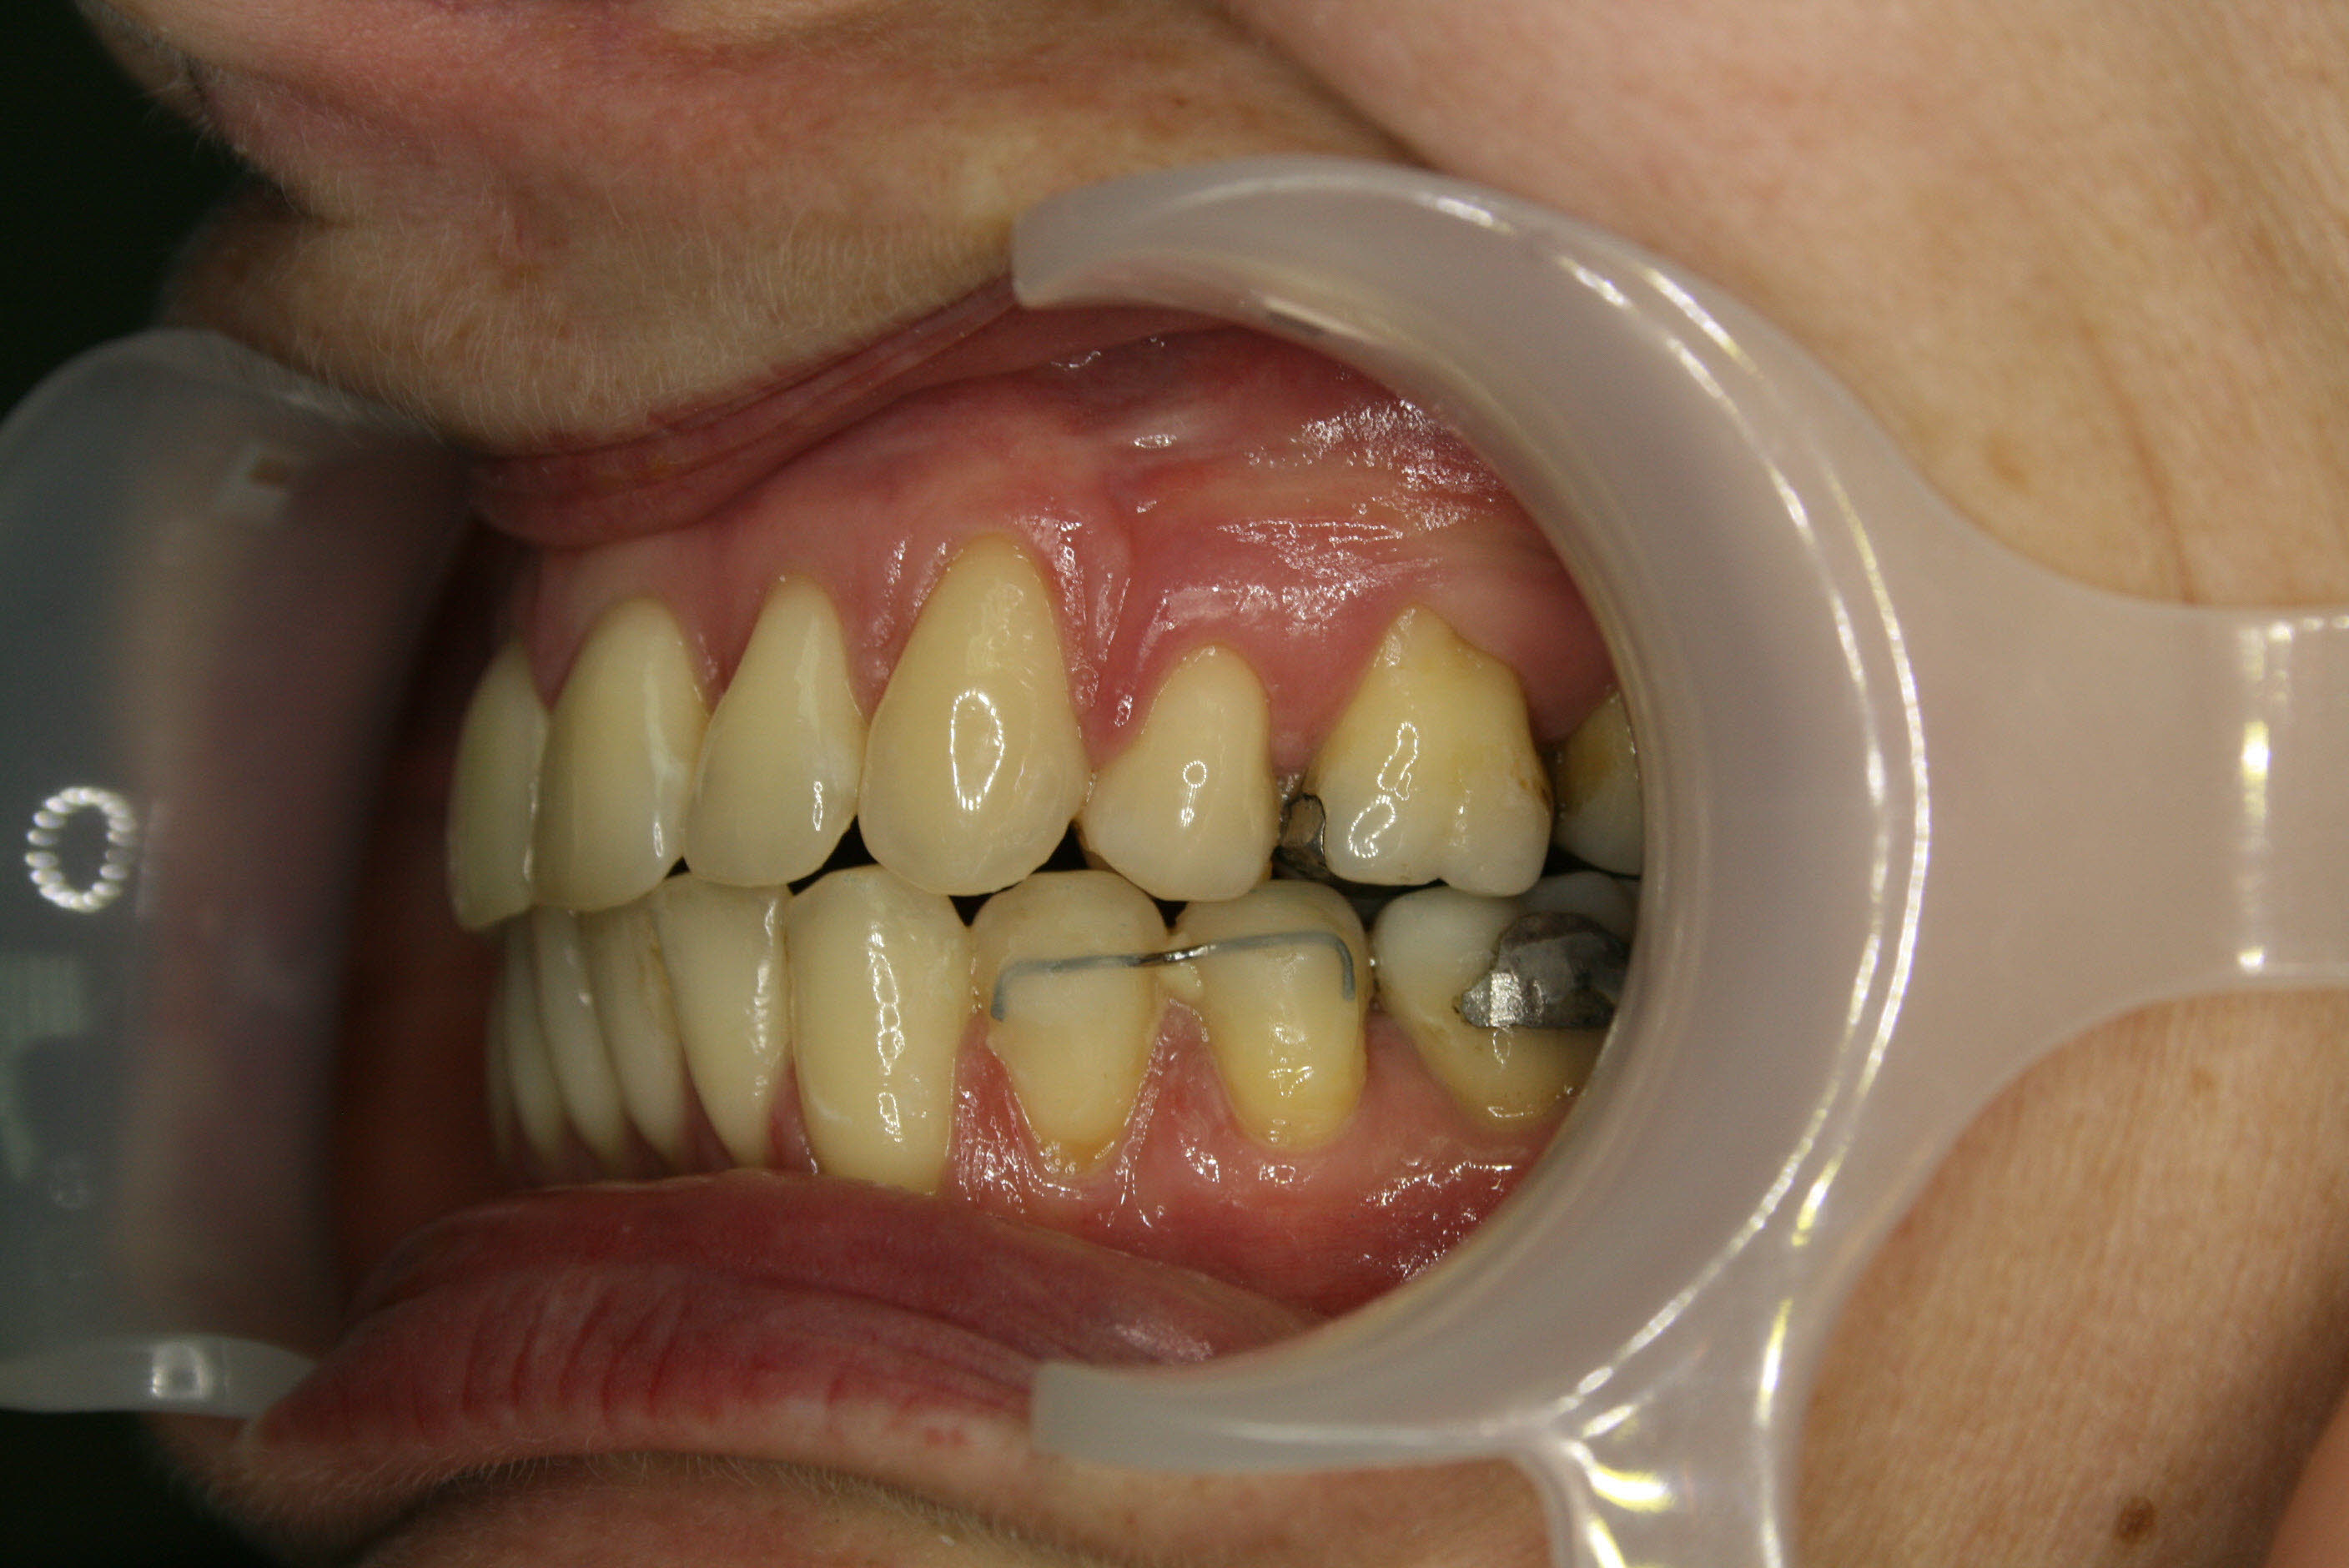

Lückenschluß in der Seitenansicht; hier ist gut zu erkennen, daß es gelungen war, den Lückenschluß von vorne her und achsengerecht auszuführen.